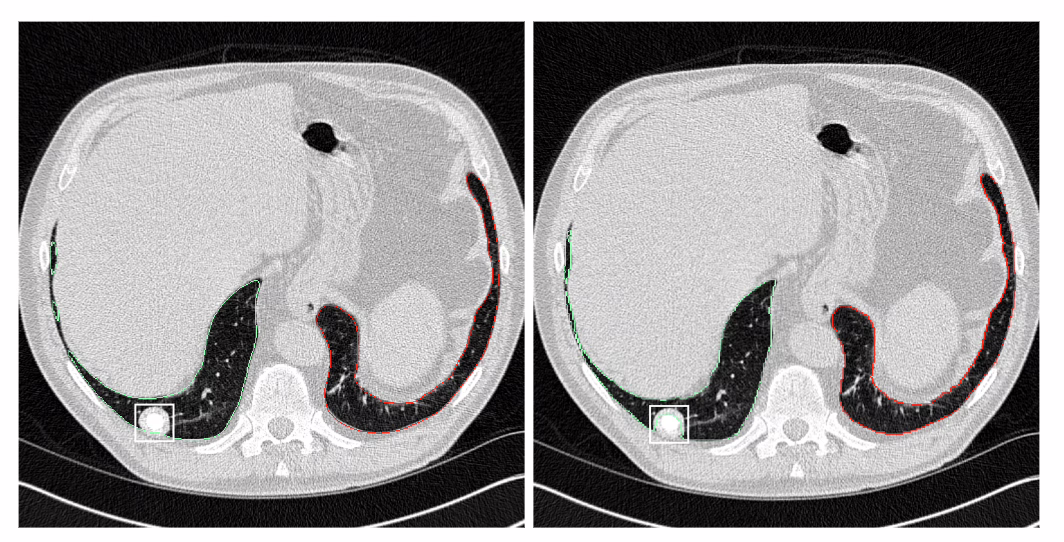

contextflow, health insurance partner IKK Südwest

Early detection is essential for successful treatment of thoracic diseases. “We offer AI software that provides additional information for identifying and interpreting lung-specific image patterns in CT scans,” says Markus Holzer, CEO and co-founder of contextflow. The ultimate goal of the software is to detect lung cancer as early as possible in order to save healthcare system resources and protect patients from unnecessary interventions. “The image analysis AI enables radiologists to assess relevant image patterns of lung cancer and respiratory diseases faster and better,” says Dr. Florian Brandt, Health Innovation Manager at IKK Südwest.